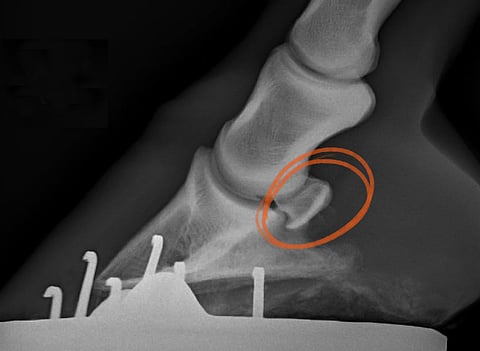

Kaikki hevosihmiset tuntevat sädeluuontuman ja tietävät, että sitä esiintyy pääasiallisesti vain etujaloissa. Oireena on kipu kavion kantaosassa. Tällöin hevonen muuttaa etujalan liikettä niin, että vika vaikuttaa tulevan ylempää lavan alueelta ja tästä syystä usein puhutaan myös lapaontumasta. Joskus hevonen voi myös lepuuttaa sairasta etujalkaansa työntämällä sitä eteensä. Ontuminen usein alkaa äkillisesti akuuttina lähinnä ravissa. Joskus oireet voivat olla voimakkaammillaan rasituksen ja sitä seuraavan lyhyen levon jälkeen. Kavion muoto voi muuttua kroonisissa sädeluuontumissa, jolloin sairaan jalan kaviosta voi tulla pieni ja pysty. FEI Campus esittelee sädeluuoireyhtymän näin: Sädeluun ja siihen liittyvien rakenteiden tulehdus, joka käsittää sädeluun limapussin tulehduksen, vauriot sädeluun siteessä kavioluuhun ja luuvauriot sädeluun liukupinnalla. Nykykäsityksen mukaan sädeluuoireyhtymä käsittää kuitenkin muitakin vaurioita sädeluun alueella. . Koko alueen oireyhtymä Urheiluhevosten ortopediaan erikoistunut eläinlääketieteen tohtori, hevoseläinlääkäri Olli Mäkelä on tutkinut kavioiden kiputiloja koko uransa ajan. "Muun muassa syvän koukistajajänteen vauriot kavion sisällä lasketaan osaksi sädeluuoireyhtymää. Tämä on oleellista, koska kolmasosa sädeluualueen kroonisista ontumista johtuu syvän koukistajajänteen vaurioista", hän täsmentää. Sädeluun sijaitsee kavion ja kavionivelen takapuolella. Se on pitkänomainen, puikulamainen ja latinankielisen nimensä mukaisesti veneen muotoinen. Sädeluu kiinnittyy yläosastaan sivusitein vuohisluun alaosaan ja alaosastaan vahvalla siteellä kavioluuhun. Sädeluun takapintaa peittää nivelrusto, jonka ansiosta sädeluu toimii liukupintana syvälle koukistajajänteelle. Ihannetilanteessa tämä liukuminen tapahtuu ilman kitkaa. Kun kitkaa alkaa muodostua, alkaa syntyä myös ongelmia. Sädeluuoireyhtymässä pahimpia vaurioita ovat sädeluun liukupinnan vauriot. "Kun sädeluun sileä rustopinta menee rikki, syntyy luukipua ja syvään koukistajajänteeseen tulee vauriota. Tällöin rikkinäinen liukupinta kraaputtaa syvää koukistajajännettä joka askeleella ja aiheuttaa kipua hevoselle", Mäkelä summaa. Syvän koukistajajänteen vauriot sädeluun takapinnalla voivat kuitenkin syntyä ilmankin sädeluun liukupinnan vaurioita. Syvän koukistajan vaurion toteaminen kavion sisällä vaatii magneettikuvantamisen. Sädeluun liukupinnan rustovauriot eivät ole todettavissa edes tarkalla magneettitutkimuksella rustopinnan ohuuden vuoksi. Rustovaurioihin liittyy kuitenkin aina sädeluun luumuutoksia, jotka ovat todettavissa joko röntgen- tai magneettitutkimuksella ja joiden perusteella tiedetään myös rustopinnan vaurioituneen. Tässä kohdassa Mäkelä muistuttaa lisäksi, että kun sädeluun liukupinnan rustovauriot ovat syntyneet, paljon ei ole tehtävissä, koska vaikka ihminen on käynyt kuussa jo ajat sitten ja lähettänyt Webb-teleskoopin etsimään maailmankaikkeudesta eksoplaneettoja, niin vakavia rustovaurioita ei kyetä kestävästi korjaamaan. Se johtuu siitä, että nivelrustot ja sädeluun rustopinta ovat rakenteita, jossa ei ole veri- eikä imusuonia, vain harvakseen soluja, joiden toiminta on aikuisella heikkoa. Nivelruston soluilla ei ole kapasiteettia korjata nivelrustoa alkuperäisen veroiseksi. "Onneksi nivelrusto on niin hyvin alunperin tehty, että se useimmiten kestää hevosen eliniän", Mäkelä naurahtaa. . Diagnoosin hankaluudet Kroonisen sädeluuvaurion diagnoosi voidaan tehdä röntgentutkimuksella. Asiaa mutkistaa se, että etenkin akuuteissa sädeluuvaurioissa sädeluu saattaa näyttää röntgenkuvassa kerrassaan täydelliseltä, mutta siinä huolimatta siinä voi olla ontumaa aiheuttava luuuruhje, joka ei röntgenissä näy. Myös ultraäänellä aluetta voi diagnostisoida. Aivan kavion sisällä olevat syvän koukistajajänteen vauriot ovat ultraäänitutkimukset erittäin haastavia todeta. Jos kuitenkin syvässä koukistajajänteessä näkyy vaurio vuohiskuopassa, on 90 prosentin todennäköisyys, että myös sädeluun takapinnalla on paha syvän koukistajajänteen vaurio. Sädeluussa voi röntgenkuvissa näkyä tyhjä ontelo eli kysta, joka usein viittaa sädeluun rustopinnan vaurioon ja sitä kautta myös todennäköiseen syvän koukistajajänteen vaurioon. Jänteessä voi olla pinnan rispaantumista ja hiertymistä, halkeamista pitkittäissuunnassa tai reikiintymistä. "Nämä eivät koskaan parane, mutta esimerkiksi pinnan rispaantumiset eivät välttämättä aiheuta kroonista ontumaa", Mäkelä sanoo. Mäkelä toteaa, että erilaisia löydöksiä voi sädeluualueella tehdä useita ja eri kohdat voivat kipeytyä erikseen tai yhtä aikaa. Myös sädeluun ja syvän koukistajajänteen välissä oleva "iskunvaimentaja", nivelnesteen täyttämä limapussi eli bursa voi tulehtua. Syvä koukistajajänne kulkee tämän limapussin läpi. Hän lisää, että myös bursassa olevat vauriot ovat huonoja paranemaan. "Limapussinesteessä on jotakin, joka estää jänteen paranemista."Kysymykseen, miksi ylipäätään limapussissa on nestettä, Mäkelä vastaa, että neste on tärkeä jänteen liukumista edesauttavana viskositeetin takia. Jännerakenne on tehty erittäin kestäväksi, mutta ei erityisen korjautuvaksi. Luontoäiti ei ole "ajatellut", että vauriota kannattaisi ruveta korjaamaan, vaan vaurioitunut yksilö jääköön pedon saaliiksi. Sädeluu voi olla halki tai jopa kokonaan vaurioitunut. Murtumia on yritetty ruuveilla korjata, mutta tekniikka on vaikeaa luun ohuuden takia. Krooniset muutokset näkyvät helpommin röntgenillä, mutta myös löydösten tulkitseminen on muuttunut. "Parikymmentä vuotta sitten tulkittiin sädeluusta niin kutsuttuja ravintokanavia, eli huokoisia juonteita, mutta nyt ollaan sitä mieltä, että ne ovat useimmiten normaaleja löydöksiä. Magneettitutkimuksissa on todettu, että suurentuneet ravintokanavat voivat tosin liittyä kavioniveltulehdukseen", Mäkelä kertoo. . OireetSädeluuoireyhtymässä hevosella on lyhentynyt askel etenkin ravissa, sillä hevonen yrittää välttää sitä vaihetta liikkeessä, jossa kavio on maakosketuksessa juuri ennen irtoamistaan maasta. Käyttäytymisen tarkoituksena on helpottaa syvän koukistajajänteen aiheuttamaa vetoa ja sen painetta sädeluuhun. Sädeluuontuma on siitä outo, että kroonisetkaan selvästi näkyvät luumuutokset eivät aina aiheuta ontumaa. "Hevosten tapa käsitellä mahdollista kipua vaihtelee ja voi olla, että urheiluhevoset kuuluvat niihin, jotka elävät kivun kanssa ilman oireita", hän sanoo. ”Erityisesti huippu kilparavureilla tuntuu olevan joskus aivan käsittämätön kivunsietokyky.” Diagnoosin tarkkuudella ei kuitenkaan sinänsä ole ehkä väliä, sillä hoito on sama kaikissa tapauksissa. . Hoito Mäkelä toteaa, että korjaavaa lääkehoitoa ei juurikaan ole. Ainakaan sellaista, jonka avulla saisi etua lepoon verrattuna. Luu sinänsä on kiitollinen hoidettava kudos siksi, että se tapaa parantua, kun sille annetaan aikaa. "Sairaskenkä ja muutaman kuukauden tarhalepo on usein hyvä kombinaatio", Mäkelä sanoo. "Aika ja lepo parantaa sen minkä parantaa", Mäkelä sanoo. "Ja jos syvä koukistajajänne on jo ottanut pahasti osumaa, voidaan sanoa, että tila on parantumaton." Kuitenkin niin, että hevoset näyttävät pystyvän elämään vaivan kanssa joskus hyvinkin. Mäkelä toteaa, että sädeluun luuvauriodiagnoosit ovat vähentyneet sen jälkeen kun totuutta alkoi tulla magneettikuvista. "En lähtisi mututuntumalta ainakaan lääkitsemään." Olli Mäkelä suosii hoitomuotona tarpeeksi pitkää lepoa syvään koukistajajänteen vaurioissa Myös luuruhjevaurion hoitona tärkein on riittävän pitkä lepo. "Aika parantaa sen", Mäkelä sanoo. Hän ei ole lääkitsemisen kannalla senkään takia, että ilman magneettitutkimusta ei usein tarkkaan tiedetä mitä vaivaa lääkitään ja jänteen ja luun parannuskeinot eivät ole samat. Rustopintaa ei edelleenkään pystytä korjaamaan. Kaikenlaista on vuosien varrella kokeiltu, mutta kortisoni on edelleen yleisesti käytössä tulehduksen poistajana. Mutta menetelmällä on varjopuolensa. "Jos lääkitset limapussia kortisonilla, puolen vuoden kuluttua syvä koukistajajänne voi olla entistä huonommassa kunnossa", Mäkelä sanoo. Aikaisemmin limapussia lääkittiin yleisesti syvän koukistajajänteen läpi pistämällä, mutta tämän on todettu aiheuttavan vaurioita syvälle koukistajajänteelle. Rispaantuneita kohtia jänteessä on tähystämällä myös putsattu, mutta tulokset ovat olleet yhtä hyviä tai huonoja kuin levolla. Bisfosfosfonaatit (Osphos ja Tildren) ovat käytössä sädeluuvian hoidossa. Ne ovat melko tehokkaita luukivun oireiden lieventämisessä. "Pidän kuitenkin epätodennäköisenä, että niillä olisi mitään osuutta luun paranemisprosessiin." Se, että korjaavaa lääkitystä ei ole, ei tarkoita, etteikö hevosia lääkittäisi. Mäkelän mukaan iso osa kroonikkopotilaista saadaan jonkinasteiseen käyttöön. Toisinaan lääkityksen ja levon vuorottelu antavat paljonkin käyttöaikaa. Äärimmäinen kivun hoitokeino on hermokatkaisu ja tämä olikin takavuosina yleinen hoitomuoto. Keino on edelleen käytössä, mutta kilpahevosilla menetelmä on kielletty. Sairaskengitys on Mäkelän mukaan hyvä hoitokeino. Ehkä paras. Perusperiaate on kaviomekanismin toiminnan edistäminen, syvän koukistajajänteen vaurioissa kannan nostaminen, ja varvasosan kääntymisen helpottaminen jotta paine sädeluualueelle helpottaisi. Esimerkiksi natural balance -kengitys helpottaa kavion kääntymistä ja vähentää rasitusta sädeluualueelle. Kavion asennon tai mallin, yleensä on syytetty matalaa kantaa ja pitkää varvasta, hän ei näe sinänsä liittyvän tähän vaivaan, vaikka niin on totuttukin ajattelemaan. "Isossa materiaalissa ei ole pystytty tällaista ainakaan todentamaan, vaan kaikenlaisia sädeluuoireilevia kavioita löytyy." Kavion mallin muuttuminen on enemmänkin seuraus kuin syy. Käyttämätön kavio pienenee ja siitä tulee pysty, ikään kuin surkastuu. Sen Mäkelä kuitenkin allekirjoittaa, että hyvin pieni kavio hyvin isolla hevosella voi olla ongelmallinen. . Syy Mistä sädeluuvaivat sitten johtuvat? Mäkelä näkee sädeluuoireyhtymän eräänlaisena käyttörasitusvaivana tyypillisesti ratsuilla. Aivan erityisesti estehevosilla. Ja mitä isompia esteitä ne hyppäävät, sitä suurempaan rasitukseen sädeluun alue joutuu. On kyse valtavista voimista, jotka kohdistuvat hyvin pienelle alueelle, kun 600-kiloinen hevonen vaikkapa laskeutuu yhdelle jalalleen isolta esteeltä tai kun massava kouluhevonen suorittaa GP-tason liikkeitä, jotka nekin ovat hevosen elimistölle raskaita, joskin voimakkaasti kootun vaikean tason kouluhevosella rasitus on pikemminkin takajaloissa, mutta niissä harvemmin sädeluuongelmia todetaan. Kun hevonen putoaa koko painollaan yhdelle jalalleen, sädeluualueelle kohdistuu valtava rasitus. "Jossain se raja menee", Mäkelä sanoo. "Mitä rankempi käyttö, sitä suurempi todennäköisyys sädeluuoireyhtymälle." KäyttörasitusvaivaHän ampuu alas yleisen väitteen ”vanhempien hevosten vaivasta”: "Itse luun rappeuma muutokset saattavat liittyä vuosiin ja kilometreihin, mutta jänteen vauriot ovat traumaperäisiä, jolloin sillä ole iän kanssa mitään tekemistä, vaan käytön." Kavio-ontumat ovat hevosten kaikkein yleisimpiä vaivoja, mutta Mäkelä ei antaisi sädeluusyndroomalle aivan niin yleisen ontuman roolia kuin on tavattu ajatella. Mäkelä huomauttaa, että yleisin kavion kantaosan ontumaa aiheuttava syy on edelleen kantaruhje tai kantapaise. Hän kuitenkin myöntää, että jos "sädeluualueella" yksi kohta kipeytyy, lumipalloefekti lähtee helposti käyntiin. Ravihevosilla vaivaa ei diagnosoida juuri ollenkaan, mutta Mäkelä ei ota siihen sen enempää kantaa, kuin että toteaa, että "ravureilla oireilee ennemminkin etupolvi". Tästä seuraa, että mitä painavampi urheiluhevonen, teoriassa sitä pahempi. Paljon puhuttuun hevosen ylipainon osuuteen asiassa Mäkelä suhtautuu kuitenkin varauksellisesti. "Ei siitä ainakaan mitään tutkittua näyttöä ole ja itse olen taipuvainen ajattelemaan, että vaikka ylipainoa olisikin, näiden hevosten omistajat harvemmin käyttävät hevosia kovin intensiivisesti, joten sädeluun puolesta ne pärjäävät pihatossaan hissutellen ehkä varsinkin hyvinkin", hän tuumaa. .Tildren ja Osphos hoitavat luuta ja sen kipua, mutta ihmeisiin ne eivät pysty.Peruskengän ylistys - myös luonnon mestariluomus kaviomekanismi kiittää